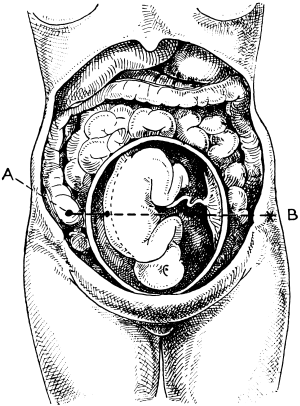

| 23. | A Gravid Uterus in Sagittal Section | 79 |